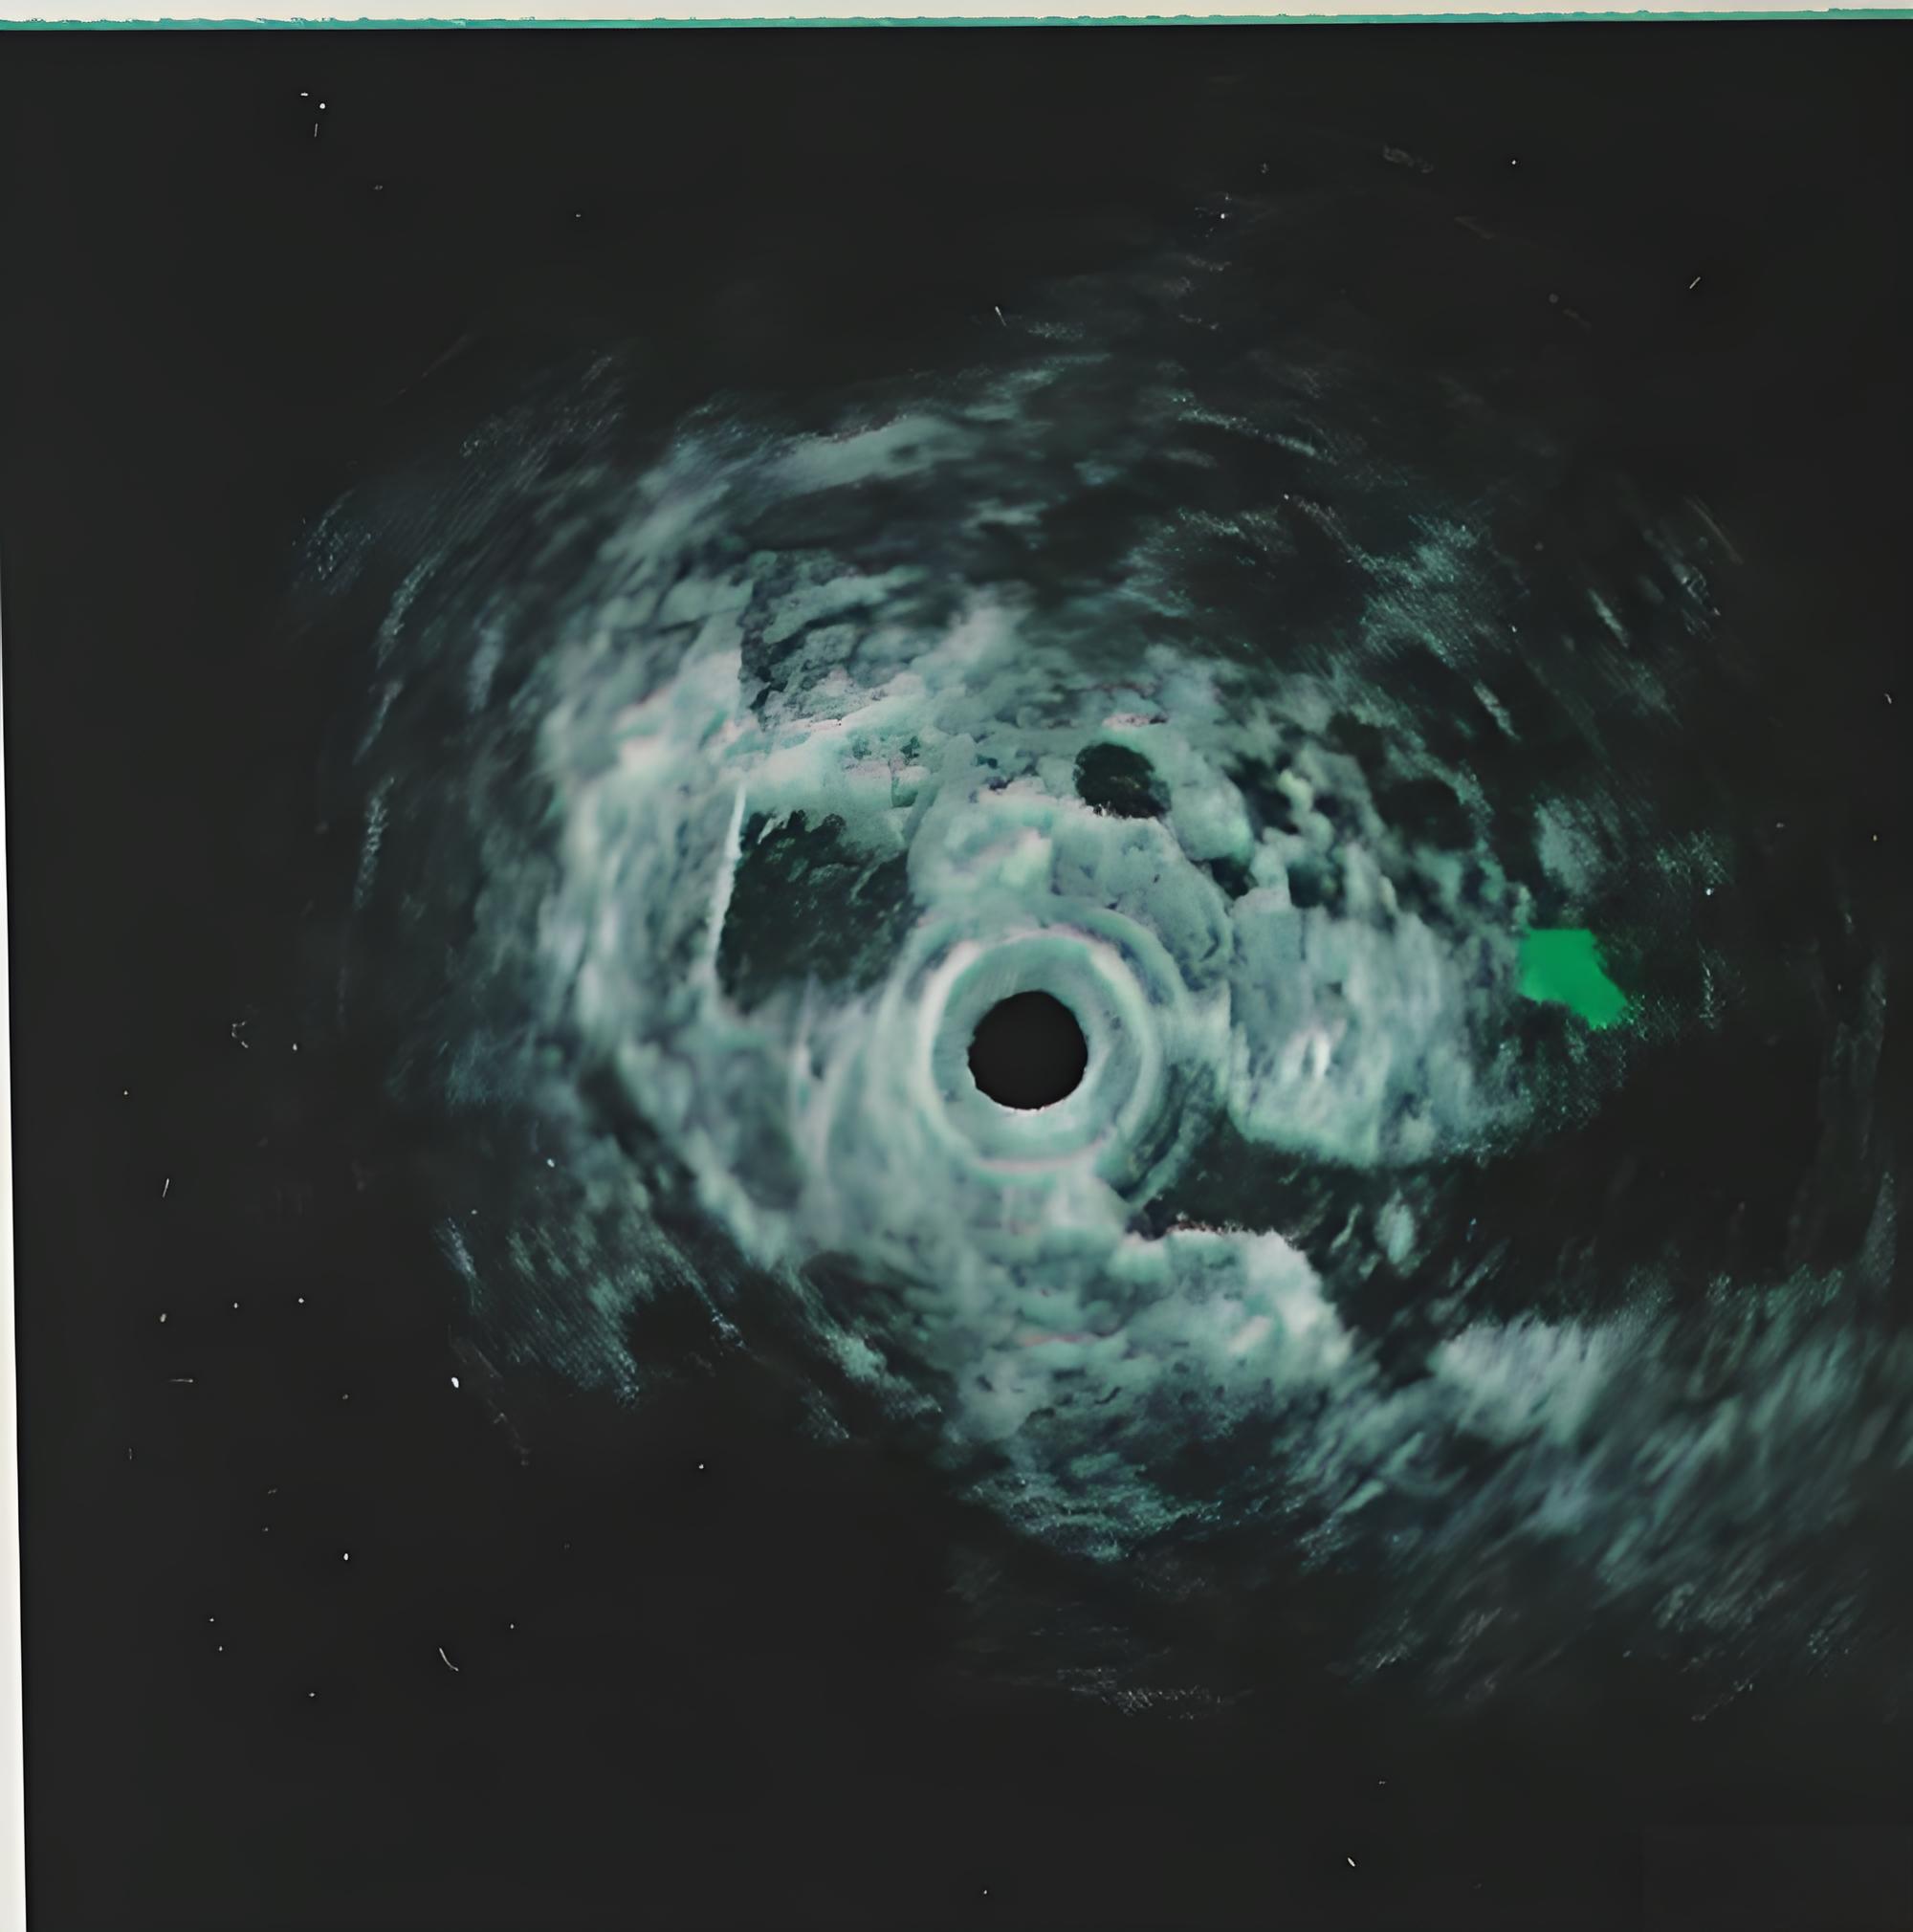

胃镜超声:判断肿瘤浸润深度,了解胃周淋巴结转移情况